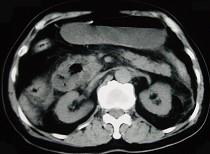

问题 男,78岁,阵发性上腹部疼痛10年伴呕吐,加重1年,影像检查如下图,应诊断为 ( )

选项 A.十二指肠癌 B.十二指肠憩室 C.十二指肠淋巴瘤 D.十二指肠结核 E.肠系膜上动脉压迫综合征

答案 B